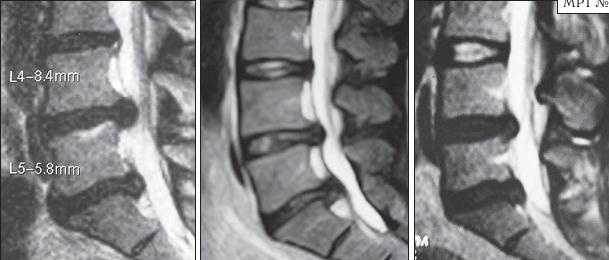

МРТ № 26

На серии МРТ № 26 наблюдаются секвестрированные грыжи межпозвонковых дисков в поясничном отделе позвоночника в сегментах LIV—LV LV—SI с каудальной (каудальной — расположенной ближе к нижней части туловища, направленной вниз) миграцией секвестра (фрагментов межпозвонкового диска)

МРТ № 27

На серии МРТ № 27 наблюдаются секвестрированные грыжи межпозвонковых дисков в поясничном отделе позвоночника в сегментах L]-Sl с краниальной (вверх) миграцией секвестра (фрагментов межпозвонкового диска)